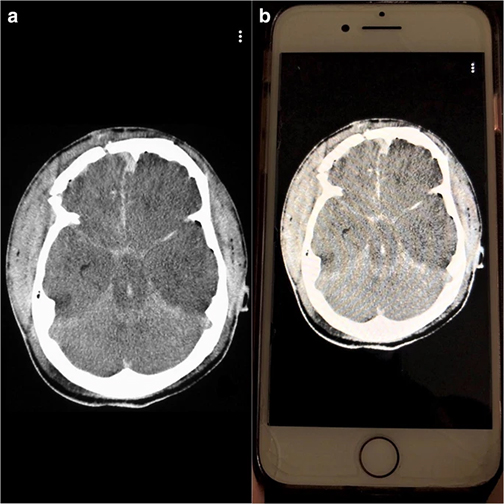

The team compared image analysis and interpretation by radiology residents using Snapchat on smartphones with conventional analysis on a single screen in the resident conference room.

“All cases used were diagnoses considered to require emergent, non-routine communication on the order of minutes to the ordering health care provider,” notes Bradley Spieler, MD, Vice Chairman of Research in the Department of Radiology at LSU Health New Orleans School of Medicine. “As such, these types of diagnoses demand prompt imaging recognition as they are considered critical findings which could result in death or significant illness if not acted upon expeditiously.”The team chose Snapchat, a social media app allowing communication via video and digital images with text messaging functionality, not only because of its popularity with young adults, but most importantly because unlike other image based social media platforms, Snapchat allows for the timing of image visibility by users. The ability to specify the length of time an image is visible to a user (or trainee in this scenario) in rendering an image-based diagnosis creates an intriguing potential for innovation in radiologic curricula, particularly as it relates to assigning a metric to diagnostic performance.

“All residents performed better on Snapchat each week,” says Dr. Spieler, who is also an Associate Professor of Radiology, Internal Medicine, Urology, & Cell Biology and Anatomy at LSU Health New Orleans. “Their accuracy rate was higher using Snapchat than a traditional classroom screen.”

Spieler says, “We believe that the results from this pilot study could facilitate a promising and novel training method in enhancing recognition of imaging diagnoses, particularly those of life-threatening nature, which could be applied to the evolving landscape of distance learning.”

Other LSU Health New Orleans authors include Drs. Dane Mackey, Caitlin Henry, Raman Danrad, Carl Sabottke, Claude Pirtle, and Eric Wallace in Diagnostic Radiology; and Dr. Jason Mussell in Cell Biology and Anatomy. Dr. Catherine Batte in the Department of Physics & Astronomy at Louisiana State University also contributed.The authors conclude, “Our hope is that this investigation can aid in the promotion of active learning and lecture participation as well as to explore metrics for gauging diagnostic performance and pattern recognition in image-based curricula both within the classroom and in remote teaching formats. A larger sample size and more intricate study designs, for example, with the adjunct of eye tracking, may support the burgeoning role that handheld devices and imaged-based social media applications like Snapchat can play in learning at all levels of education especially in the context emergency radiology.”